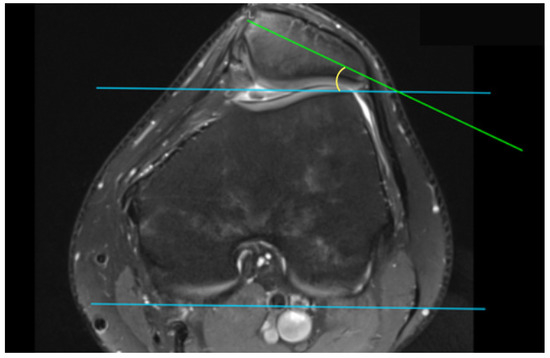

| SA | Sulcus angle |

| SAb | 148.26 ± 13.82 | 149.93 ± 10.66 | 0.64 |

| SAc | 156.06 ± 12.43 | 159.01 ± 10.69 | 0.37 |